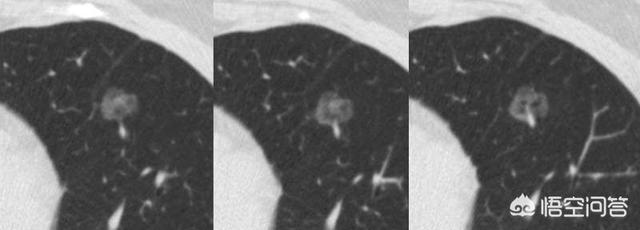

このような4ミリほどの小さな固形結節は滑らかで、悪性腫瘍の明らかな兆候は見られなかった。しかし、2年4ヵ月後:

後に病理検査で小細胞肺がんであることが確認された。